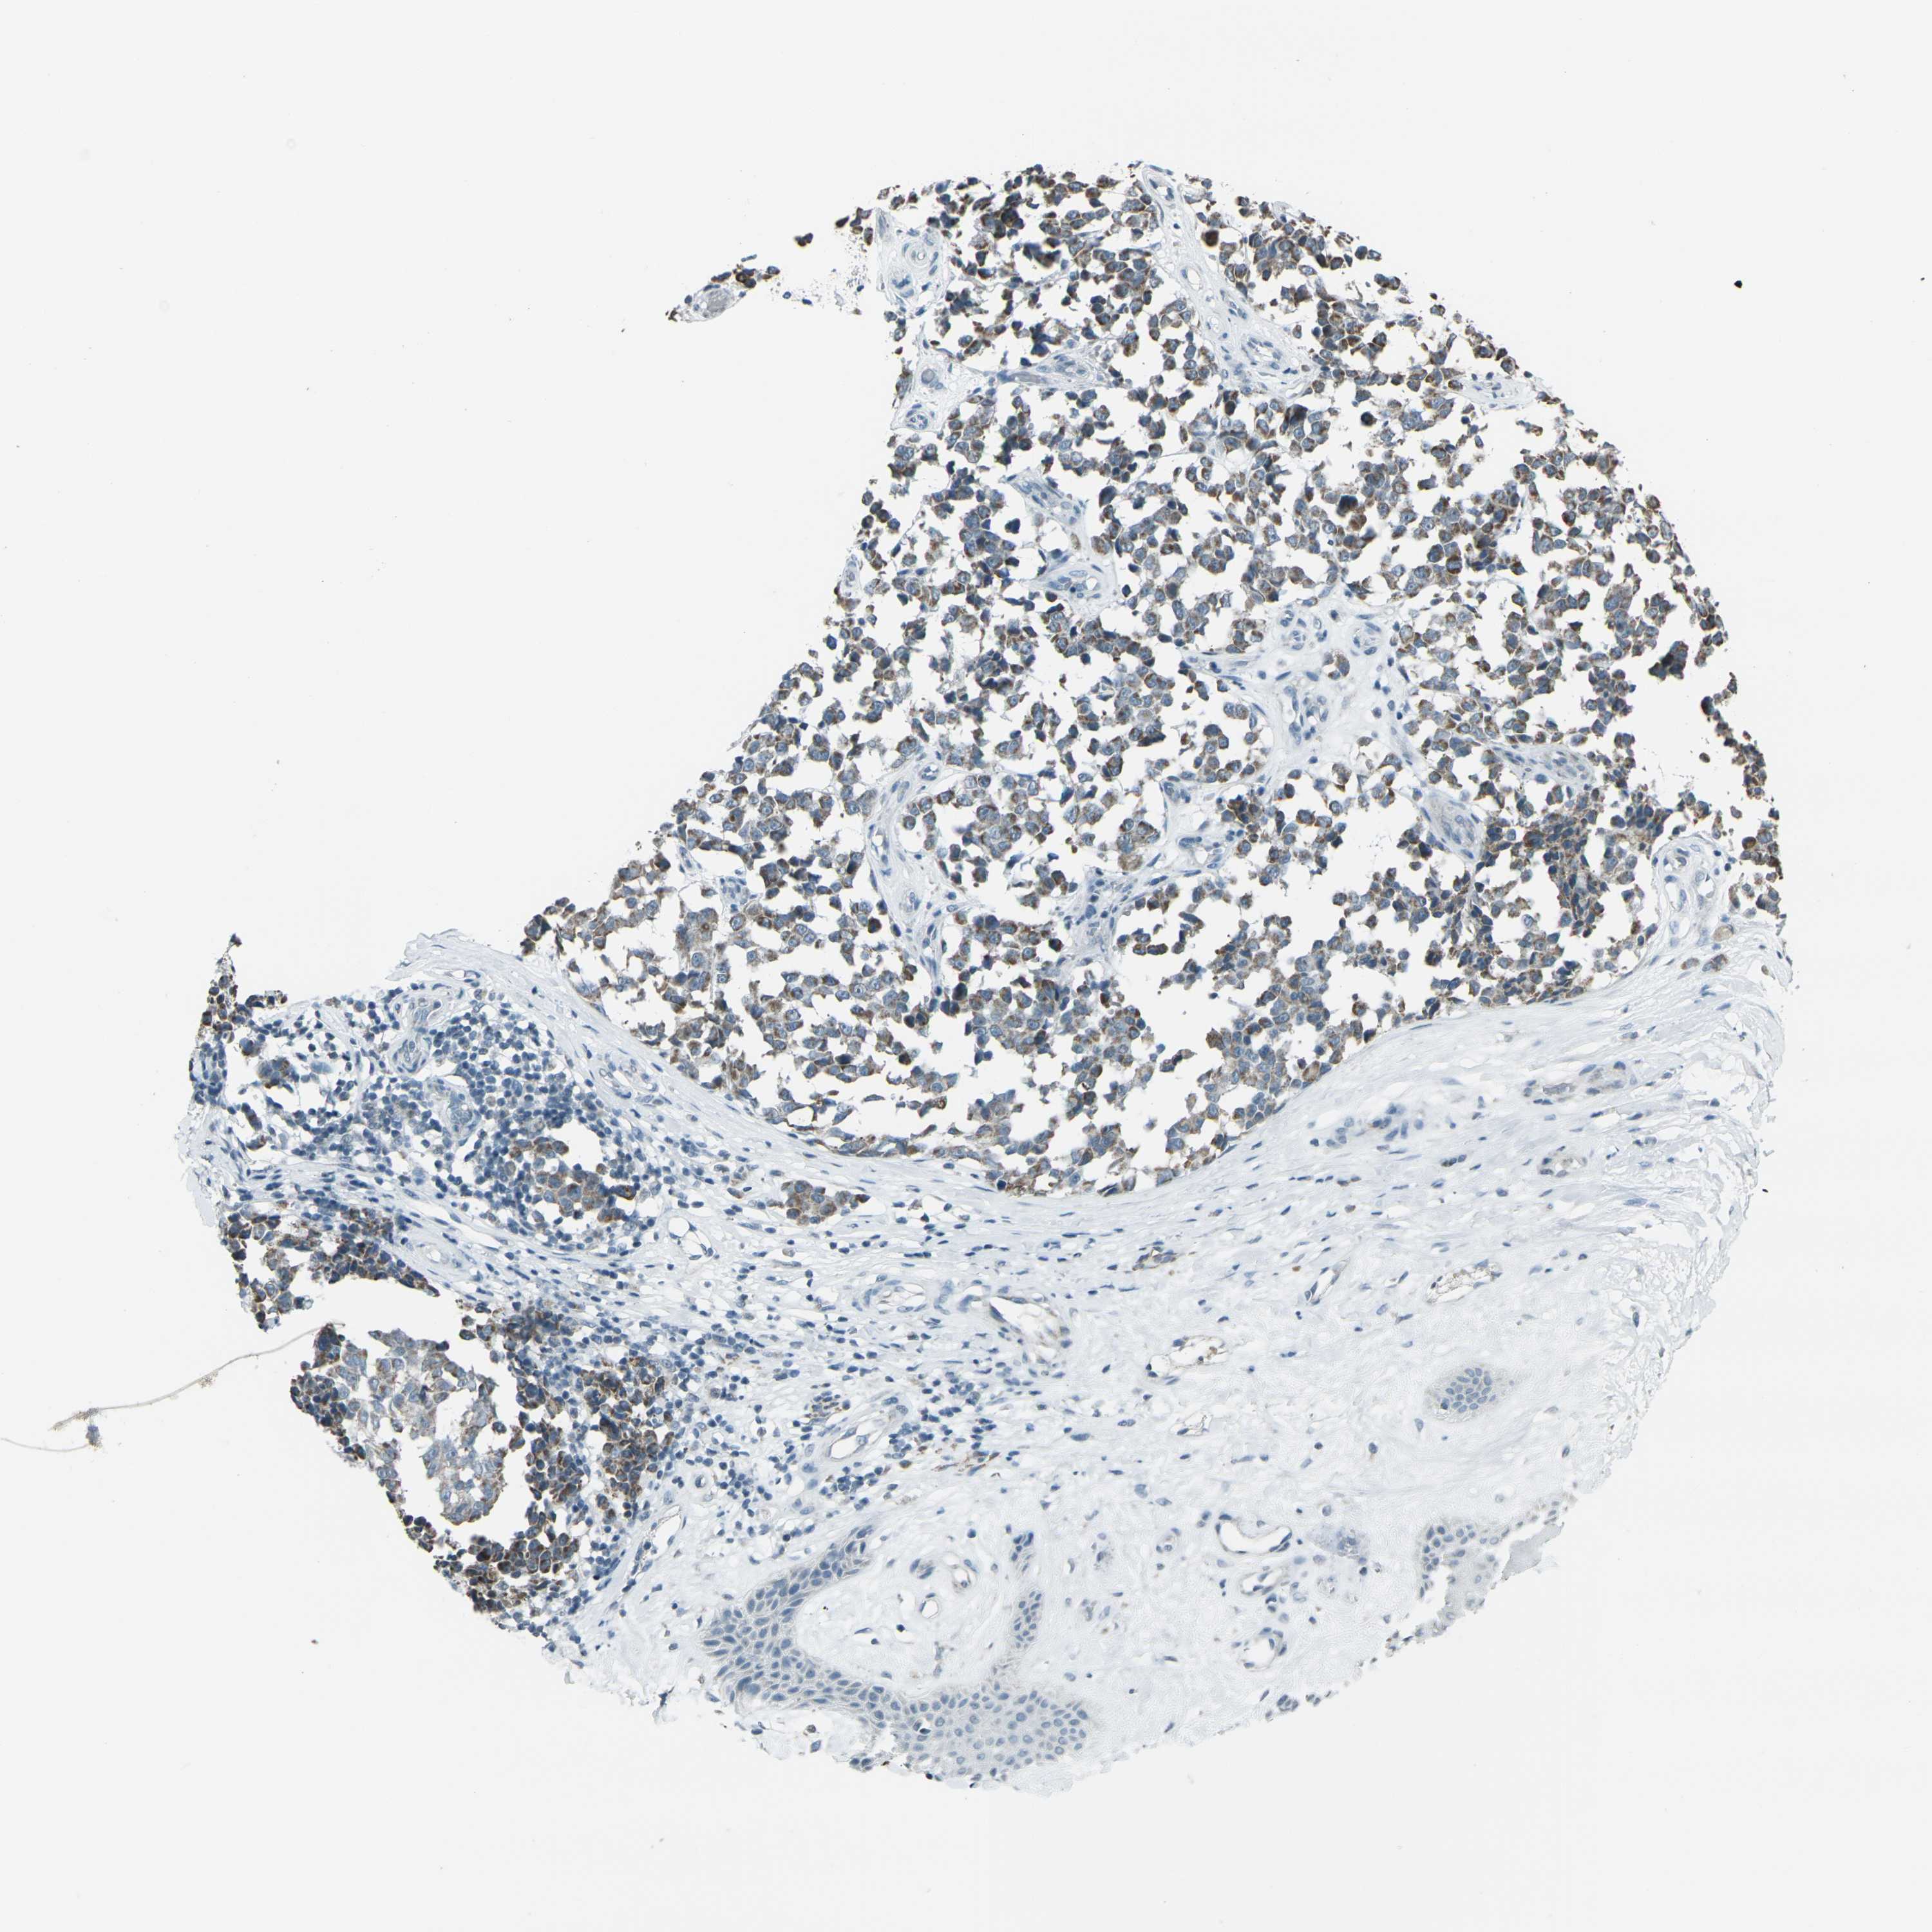

MELANOMA - Protein expressioni

A mouse-over function shows sample information and annotation data. Click on an image to view it in a full screen mode. Samples can be filtered based on level of antibody staining by selecting one or several of the following categories: high, medium, low and not detected. The assay and annotation is described here.

Note that samples used for immunohistochemistry by the Human Protein Atlas do not correspond to samples in the TCGA dataset.

Antibody stainingi

Antibody staining in the annotated cell types in the current human tissue is reported as not detected, low, medium, or high, based on conventional immunohistochemistry profiling in selected tissues. This score is based on the combination of the staining intensity and fraction of stained cells.

Each image is clickable and will lead to virtual microscopy that enables deeper exploration of all samples and also displays staining intensity scores, fraction scores and subcellular localization as well as patient and tissue information for each sample.

Antibody HPA042205

Antibody HPA043013

Antibody CAB011603

Staining

High

Medium

Low

Not detected

Intensity

Strong

Moderate

Weak

Negative

Quantity

>75%

75%-25%

<25%

None

Location

Nuclear

Cytoplasmic/membranous

Cytoplasmic/membranous,nuclear

Malignant melanoma, NOS

Malignant melanoma, Metastatic site

Malignant melanoma in situ